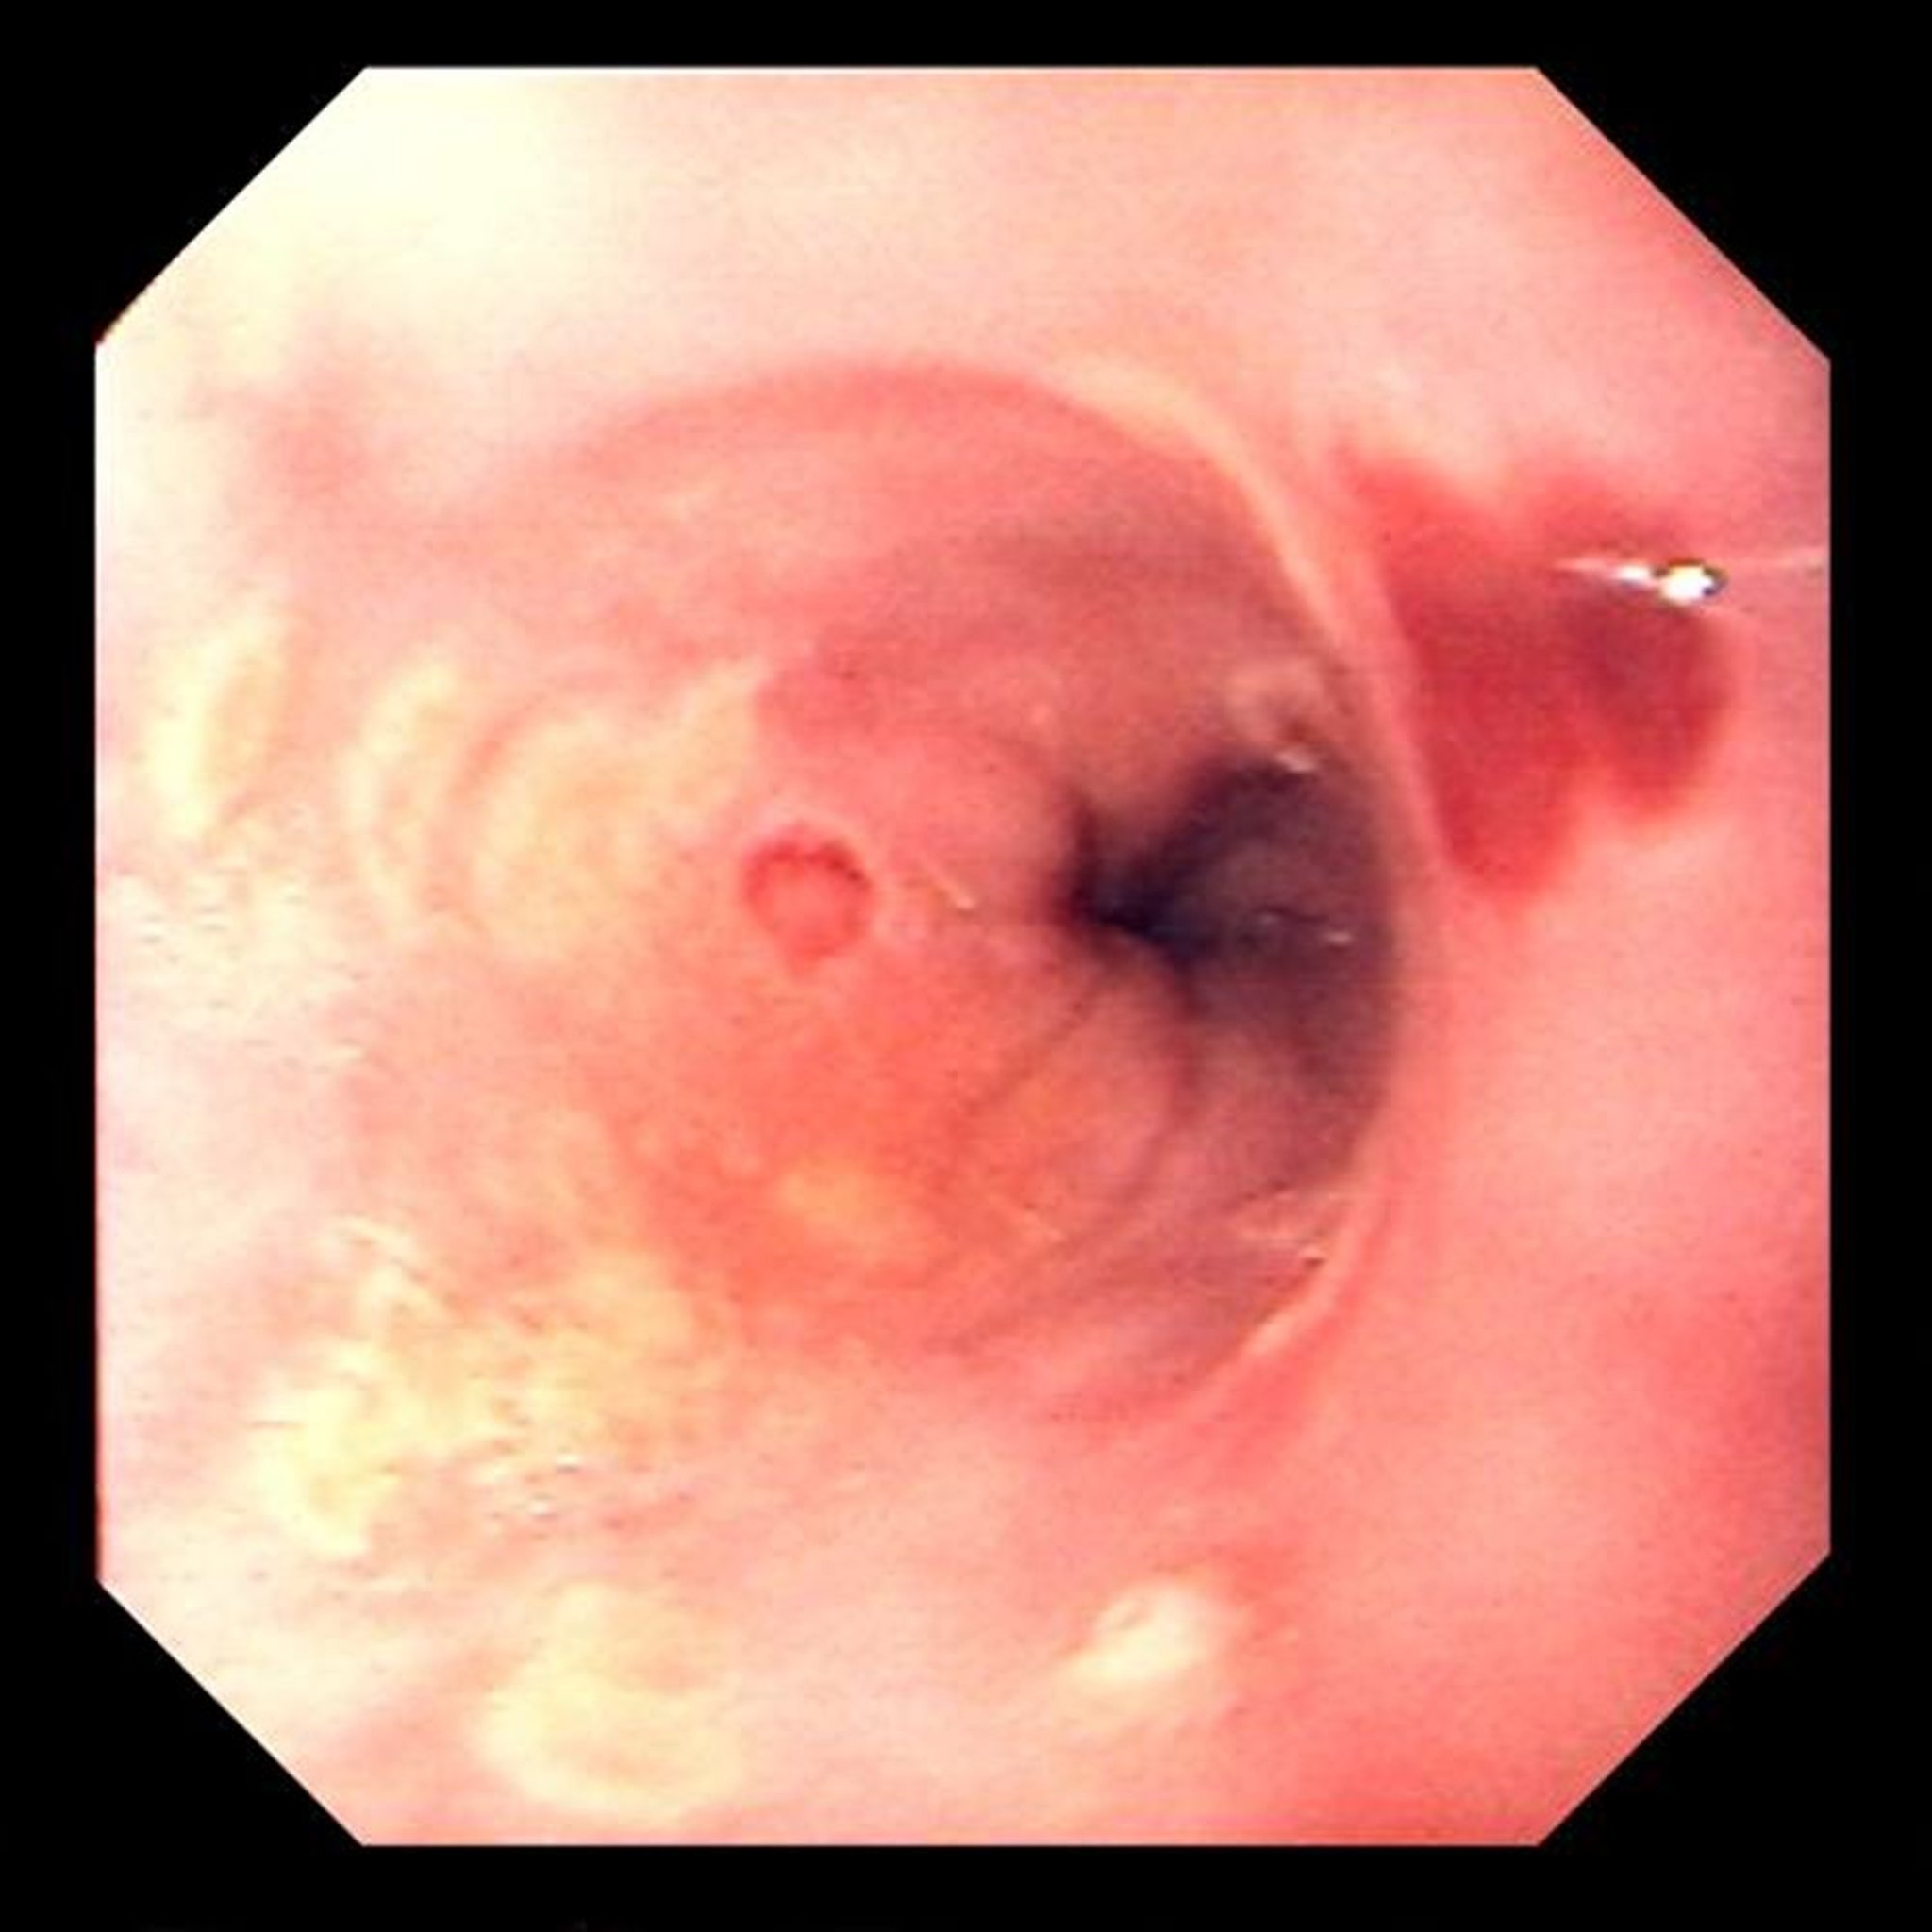

Herpes-simplex-Virus-Ösophagitis und Zytomegalievirus-Ösophagitis

Diese Infektionen treten bei transplantierten Patienten gleich häufig auf, HSV Ösophagitis meistens früh nach der Transplantation (Reaktivierung), CMV Ösophagitis nach 2–6 Monaten. Bei HIV-Patienten ist CMV wesentlich häufiger als HSV, und eine virale Ösophagitis tritt vor allem dann auf, wenn die CD4+-Zellzahl < 200/mcl ist. Eine schwere Odynophagie resultiert aus beiden Infektionen.

Image provided by David M. Martin, MD.

Eine endoskopische Untersuchung inkl. Zytologie oder Biopsie ist für die Diagnosestellung meist notwendig.

HSV wird mit oralem oder intravenösem Aciclovir, Valaciclovir oder Famciclovir behandelt. Patienten mit geschwächtem Immunsystem werden in der Regel länger behandelt (d. h. 14–21 Tage) als Patienten, bei denen dies nicht der Fall ist (7–10 Tage).

CMV wird in der Regel mit intravenösem Ganciclovir oder oralem Valganciclovir bei Patienten mit geschwächtem Immunsystem behandelt. Alternativen sind Foscarnet und Cidofovir.